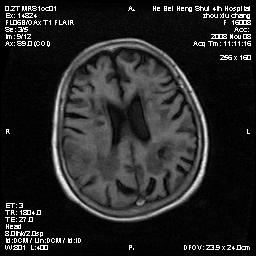

标题: MRI1883:女67岁,半年前曾患脑梗塞,治疗后好转,近3各月精 [打印本页]

标题: MRI1883:女67岁,半年前曾患脑梗塞,治疗后好转,近3各月精

女67岁,半年前曾患脑梗塞,治疗后好转,近3各月精神恍惚。

两种可能:1,转移瘤,2,脑炎,建议增强扫描

多发硬化(年龄不太支持)待排转移瘤

转移瘤?淋巴瘤?

形态及整体病灶看起来首先考虑转移瘤或淋巴瘤,但奇怪的是多个病灶周围均未见显著的水肿区,这不符合这两个肿瘤的特点,结合ct表现及患者病史有个人考虑是否有皮层下动脉硬化性脑病伴多发胶质增生可能.

考虑  皮层下动脉硬化性脑病伴脑炎或

不像占位性病变,考虑脱髓鞘改变

脑转移瘤?

1皮层下动脉硬化性脑病,2胶质增生。

皮层下动脉硬化性脑病伴脱髓鞘改变!

脑白质病

不除外转移瘤,建议增强

支持:皮层下动脉硬化性脑病伴脱髓鞘改变。